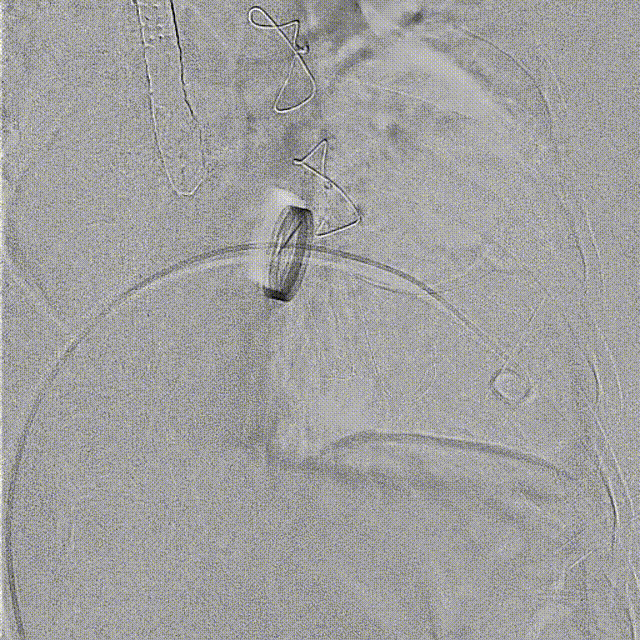

手術在全麻狀態(tài)下開展,海軍軍醫(yī)大學附屬長海醫(yī)院陸方林教授與廈門心血管病醫(yī)院王焱院長共同上臺,為患者進行手術。此次手術采用經右側頸靜脈入路的方式將輸送器送入患者心臟內,在TEE及DSA引導下調整輸送器頭端角度,使得輸送器與三尖瓣瓣環(huán)平面垂直。在輸送器進入右心室后釋放室間隔錨定裝置,而后釋放瓣葉夾持件(2個耳片結構)成垂直狀態(tài)。在TEE及DSA確定夾持件固定至三尖瓣葉根部且位于右室側后釋放人工瓣心房側盤片。隨后調整瓣膜同軸性以及室間隔錨定件位置(貼合室間隔),前推藏針管并固定,進而釋放室間隔錨定裝置,并再次確認瓣膜位置、穩(wěn)定性及同軸性,合攏輸送鞘后撤出輸送器,完成LuX-Valve Plus人工三尖瓣瓣膜的植入。

術后DSA